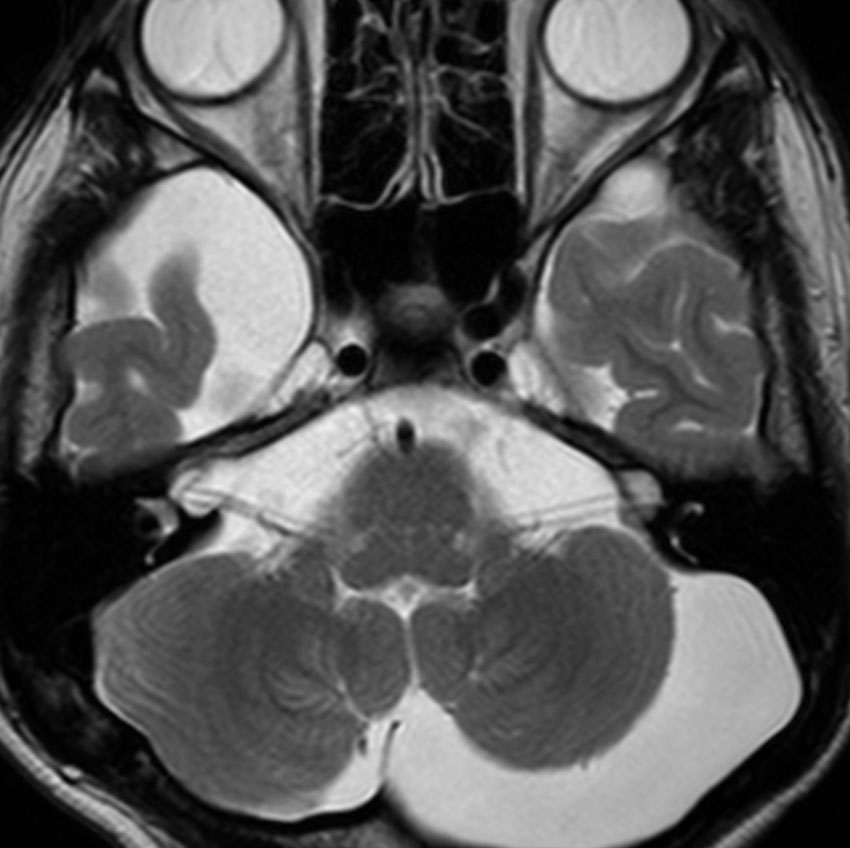

幼児の視路の毛様粘液性星細胞腫です。T2強調画像(左側)で白く高信号に写るのが特徴です。ガドリニウム増強ではまだらになっていますが,均一に真っ白に高信号になることも多いです。乳幼児のものは,ドロドロに柔らかい腫瘍です。

生後7カ月の幼児です。目が揺れるようになり(振り子様眼振)眼科を受診して腫瘍が発見されました。小児脳腫瘍の治療ができる病院へと紹介されました。

1ヶ月後にまたMRI検査がされました。乳児ですから検査にも麻酔が必要です。腫瘍は明らかに大きくなっています。左視神経から視索の腫瘍化が著しいので右側だけかすかに視力が残っているかもしれません。視力は明かりがわかる程度(明暗弁)と評価されました。

こんなことを書くのは悪いことかもしれませんが,まったく馬鹿げた提案です。この画像はどこをどう見ても視路から発生した毛様粘液性星細胞腫です。画像はpathognomonic(日本語で火を見るよりも明らか)です。この小さな子に,全身麻酔をして開頭手術で生検病理診断すれば,それだけで3週間は化学療法の開始が遅れます。その間に明かりも見えなくなってしまう(完全失明する)可能性が高いでしょう。2021年時点でも,開頭手術による生検術は行われていますが,こんな重病の小さな子どもの頭を無用に開くなど,私にはもう理解不能です。